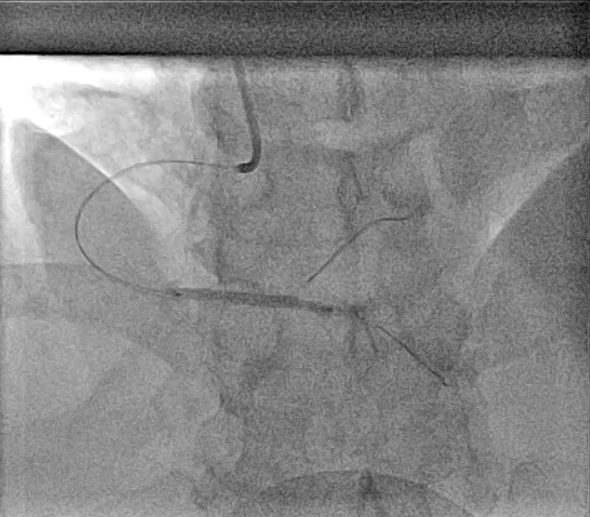

PCI was performed with a 7Fr JR4 Guide with wires in the RPDA and RPL. Lesion was predilated and stented with a 2.75x33m DES and postdilated with a 4.5mm NC proximal to the RCA bifurcation. IVUS showed underexpansion distally and severe malapposition proximally hence the stent was further postdilated with 2.75mm NC distally and 4.5mm in the distal RCA. ClearStent showed unravelling of the stent, which was confirmed on IVUS with a new total stent length of 52mm. The distal RCA diameter had grown in size to 5mm at the site of the proximal stent edge. A 4.5x24mm DES was implanted in the distal RCA to cover the unravelled stent struts, which was postdilated with a 5mm NC balloon. Final IVUS showed the stent to have adequate apposition with no immediate complications.